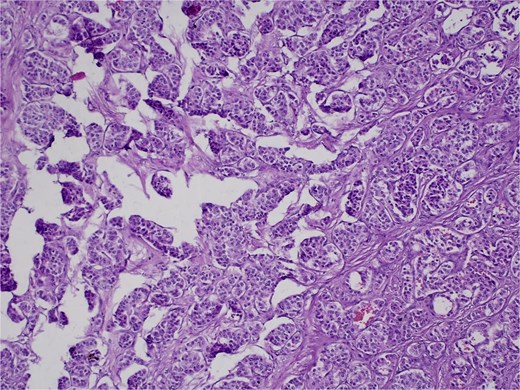

On 27 January 2025, the patient underwent a Whipple procedure (pancreaticoduodenectomy). The surgery included cephalic pancreatectomy with reconstruction through hepaticojejunostomy and gastrojejunostomy in a Roux-en-Y configuration. Gross pathology revealed a firm, white-yellow, indurated mass in the pancreatic head measuring 3.7 × 3.5 × 3 cm with irregular borders and central hardness (Fig. 4). Histopathological analysis confirmed a Grade 1 neuroendocrine tumor (insulinoma), with a Ki-67 index of 2%. The tumor showed direct extension to adjacent pancreatic tissue, the duodenal muscularis propria, the adventitia, and the muscularis of the common bile duct. Five peripancreatic lymph nodes were dissected, three of which were positive for metastases (Figs 5–9).

H&E stain, 100× magnification. Papillary and trabecular architecture with minimal atypia and characteristic “salt and pepper” chromatin.